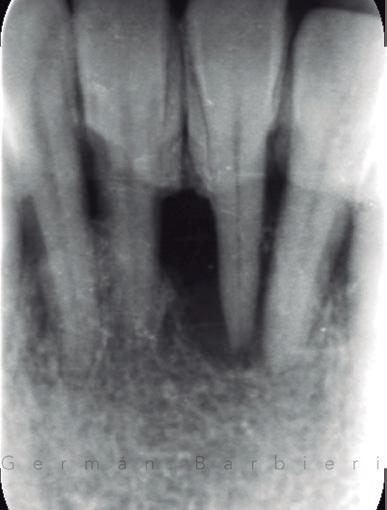

REvolución radiográfica tras solo nueve meses utilizando únicamente proteínas derivadas de la matriz del esmalte junto a una técnica quirúrgica mínimamente invasiva.

Esta es una pregunta con difícil respuesta. Realmente el límite lo ponen los factores anteriormente nombrados. Cada uno de ellos debería analizarse en conjunto para decidir si un caso es o no susceptible de regeneración. Si nos centramos específicamente en los factores del defecto (número de paredes, ángulo del defecto, profundidad del defecto, movilidad dental, lesión endo-periodontal), ninguno de ellos per se puede ser suficiente como para justificar la imposibilidad de realizar una regeneración periodontal con el objetivo de mantener el diente en boca. Ni siquiera la inserción dental remanente, por mínima que sea, incluso llegando a ser nula. El caso que presento (caso 3) es un ejemplo de ello. Mujer de 68 años, exfumadora hace 20 años de 10 cigarrillos/día, sin patologías sistémicas. Acude a nuestra clínica con el siguiente motivo de consulta: “Tengo mucho miedo de perder mis dientes. Llevo muchos años con movilidad y me gustaría que hicieran lo posible por evitar extracciones”. La paciente presentaba una periodontitis estadio III, grado A10; con vitalidad negativa en el diente 31 (fig. 3.1). Tras su diagnóstico completo, decidimos hacer un tratamiento periodontal básico e instrucciones de higiene oral (fig. 3.2). Posteriormente derivamos el caso a nuestro endodoncista, el doctor Luis Costa, quien comenzó el tratamiento endodóntico del diente 31 colocando hidróxido de calcio y ferulizando el diente 31 al 32. Una semana después finalizó la endodoncia del mismo con su correspondiente obturación y sellado coronal. Tras un periodo de cuatro meses, la paciente seguía presentando sondajes periodontales muy profundos en todo el 5º sextante. La radiografía periapical del 31 a los cuatro meses mostraba la ausencia de regeneración del defecto con el tratamiento realizado hasta la fecha. Incluso se podía apreciar un posible desplazamiento del ápice del diente 31 (fig. 3.3). Dada la situación clínica, decidimos hacer un tratamiento regenerativo de todo el sextante mediante una técnica quirúrgica de preservación de papila modificada36 aplicando únicamente proteínas derivadas de la matriz del esmalte (fig. 3.4). El problema surgió cuando la ferulización del 31 se rompió durante el raspado y alisado radicular del diente (fig. 3.5). Dado que el tratamiento regenerativo estaba destinado a todo el sextante y no solo al 31 (fig. 3.6), decidimos seguir adelante con nuestra intervención con la intención de mantener “todos” sus dientes. Colocamos el diente avulsionado en suero fisiológi-

RFIG. 3.3